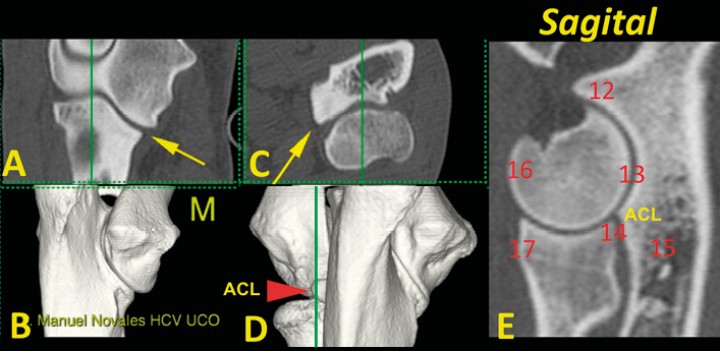

En el plano sagital podemos analizar la ACM a dos niveles: a) el ápex de la ACM, que no debe aparecer fragmentado (11) y b) la ACL. En este plano podemos estudiar: 12) la apófisis ancónea (unida y sin osteofitos); 13) la congruencia articular húmero-cubital y húmero-radial; 14) el escalón entre la apófisis coronoides lateral y la epífisis proximal del radio; 15) la ausencia de esclerosis subtroclear del olécranon; 16 y 17) la presencia de osteofitos en el cóndilo humeral (16) o en la epífisis proximal del radio (17) (Figs. 10 y 11) (Vídeo 4).

<p>Codo normal. Imágenes tridimensionales del codo en visión caudomedial (<strong>B</strong>) y craneal (<strong>D</strong>), así como planos de corte dorsal (<strong>A</strong>), transversal (<strong>C</strong>) y sagital (<strong>E</strong>). Las líneas verdes en A, C y D muestran el nivel al que se ha obtenido el plano sagital (E). Se señala el ápex de la ACM (flecha amarilla) que no debe estar fragmentado (11). (M: lado medial).</p>

Codo normal. Imágenes tridimensionales del codo en visión caudomedial (B) y craneal (D), así como planos de corte dorsal (A), transversal (C) y sagital (E). Las líneas verdes en A, C y D muestran el nivel al que se ha obtenido el plano sagital (E). Se señala el ápex de la ACM (flecha amarilla) que no debe estar fragmentado (11). (M: lado medial).

<p>Codo normal. Imágenes tridimensionales del codo en visión caudomedial (<strong>B</strong>) y craneal (<strong>D</strong>), así como planos de corte dorsal (<strong>A</strong>), transversal (<strong>C</strong>) y sagital (<strong>E</strong>). Las líneas verdes en A, C y D muestran el nivel al que se ha obtenido el plano sagital (E). Se señala la ACM (flecha amarilla) y la ACL (punta de flecha roja). En este plano dorsal se valora: la apófisis ancónea, unida y sin osteofitos (12); la congruencia articular húmero-radio-cubital (13); el escalón entre la ACL y la epífisis proximal del radio (14); el grado de esclerosis subtroclear (15); la presencia de osteofitos en la superficie craneal del cóndilo del húmero (16) o la epífisis proximal del radio (17) (M: lado medial).</p>

Codo normal. Imágenes tridimensionales del codo en visión caudomedial (B) y craneal (D), así como planos de corte dorsal (A), transversal (C) y sagital (E). Las líneas verdes en A, C y D muestran el nivel al que se ha obtenido el plano sagital (E). Se señala la ACM (flecha amarilla) y la ACL (punta de flecha roja). En este plano dorsal se valora: la apófisis ancónea, unida y sin osteofitos (12); la congruencia articular húmero-radio-cubital (13); el escalón entre la ACL y la epífisis proximal del radio (14); el grado de esclerosis subtroclear (15); la presencia de osteofitos en la superficie craneal del cóndilo del húmero (16) o la epífisis proximal del radio (17) (M: lado medial).